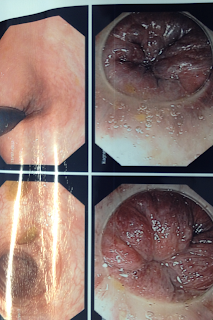

Foto: Hemorroida de primeiro grau e segundo grau, estão localizadas dentro do reto:

Hemorroida de terceiro grau:

Entendendo: A hemorroida de 3 grau.

- Ânus sem fazer esforço, de aspecto normal e a Hemorroida permanecerá dentro do reto.

- Eu pedi para o paciente fazer esforço para evacuar: A hemorroida apareceu, essa é a hemorroida de 3 grau.